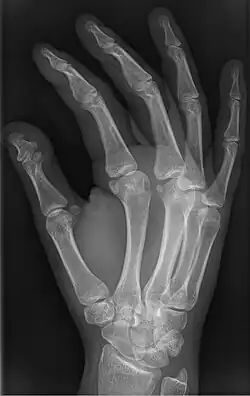

| Brachyphalangy of the thumb's distal phalanx, also known as brachydactyly type D, with otherwise normal phalanges of the 2nd-5th digits | |

Brachyphalangy is a condition in which one or more of the phalanges of the fingers and toes are smaller than normal.[1]

This condition is caused by either fusion or early closure of the phalange's growth plate. One example is brachydactyly type D, which is caused by an early closure of the thumb's distal phalange, leading to a congenitally short thumb with a similarly short and wide thumb nail.